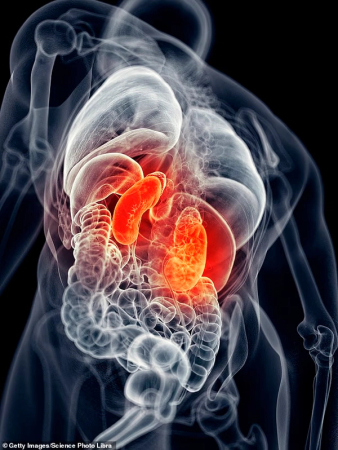

Catching Covid significantly raises the risk of developing kidney disease, researchers find

Daily Mail | Feb 28, 2026